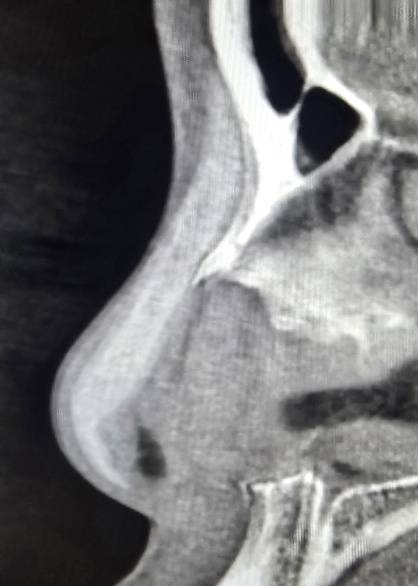

1 ตรวจการเบี้ยวเอียง ปัญหาใหญ่ของการเสริมจมูก ไม่ว่าจะเป็นแบบ openหรือ closed rhinoplasty ก็คือ การเอียง,เบี้ยว คำตอบของผู้ให้กับผู้รับบริการ ที่ไม่ตรงกัน เรามีคำตอบและพิสูจน์ได้ด้วยตาคุณเอง 100% ไม่ว่าจะเป็นที่ไหน โคนหรือปลายจมูก? มากหรือน้อย?

ในกรณีเอียงไม่มาก อาจเป็นสาเหตุให้แกนจมูกใหญ่ หรือ รูจมูกไม่เท่ากันได้ เราสามารถตรวจได้อย่างมั่นใจจากการเห็นภายใน โดยไม่ขึ้นกับอาการบวม เหมือนการตรวจด้วยการมองหรือการคลำ

2 ตรวจดูทรงซิลิโคน จมูกไม่สวยซักที CTบอกได้ เพราะ การตรวจด้วยเครื่องเอกซเรย์คอมพิวเตอร์ความละเอียดสูง สามารถบอกได้ว่าปัญหาความไม่สวยเกิดจากอะไร ทรงSILICONEจมูก ยาวหรือสั้นเกินไป SILICONEตรงหรือโก่ง หัวใหญ่หัวเล็ก การตรวจด้วยเครื่องเอกซเรย์คอมพิวเตอร์ความละเอียดสูง บอกได้ทั้งหมด จะเห็นว่ารูปทรงของSILICONE เมื่อเสริมเข้ามาจริงๆแล้ว ยังต้องมีการปรับตัวให้เข้ากับเนื้อเยื่อรอบด้านทำให้ไม่สามารถประเมินจากภายนอกเพียงอย่างเดียวได้

3 ความเสี่ยงของการทะลุ ในกรณี มีการดันของซิลิโคนมากเกินไปจนผิวหนังบางขึ้น การตรวจด้วยเครื่องเอกซเรย์คอมพิวเตอร์ความละเอียดสูง สามารถบอกได้ โดยเฉพาะอย่างยิ่งการทะลุจากด้านในรูจมูก พราะส่วนใหญ่ของการทะลุไม่ได้เกิดบริเวณผิวด้านนอก แต่เกิดด้านในรูจมูก ซึ่งยากต่อการตรวจสอบ